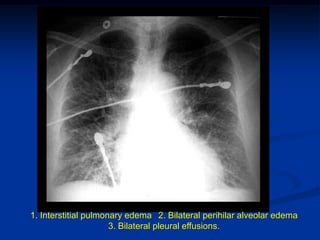

1. Interstitial pulmonary edema 2. Bilateral perihilar alveolar edema

3. Bilateral pleural effusions.

1. Interstitial pulmonaryedema 2. Bilateral perihilar alveolar edema 3. Bilateral pleural effusions.